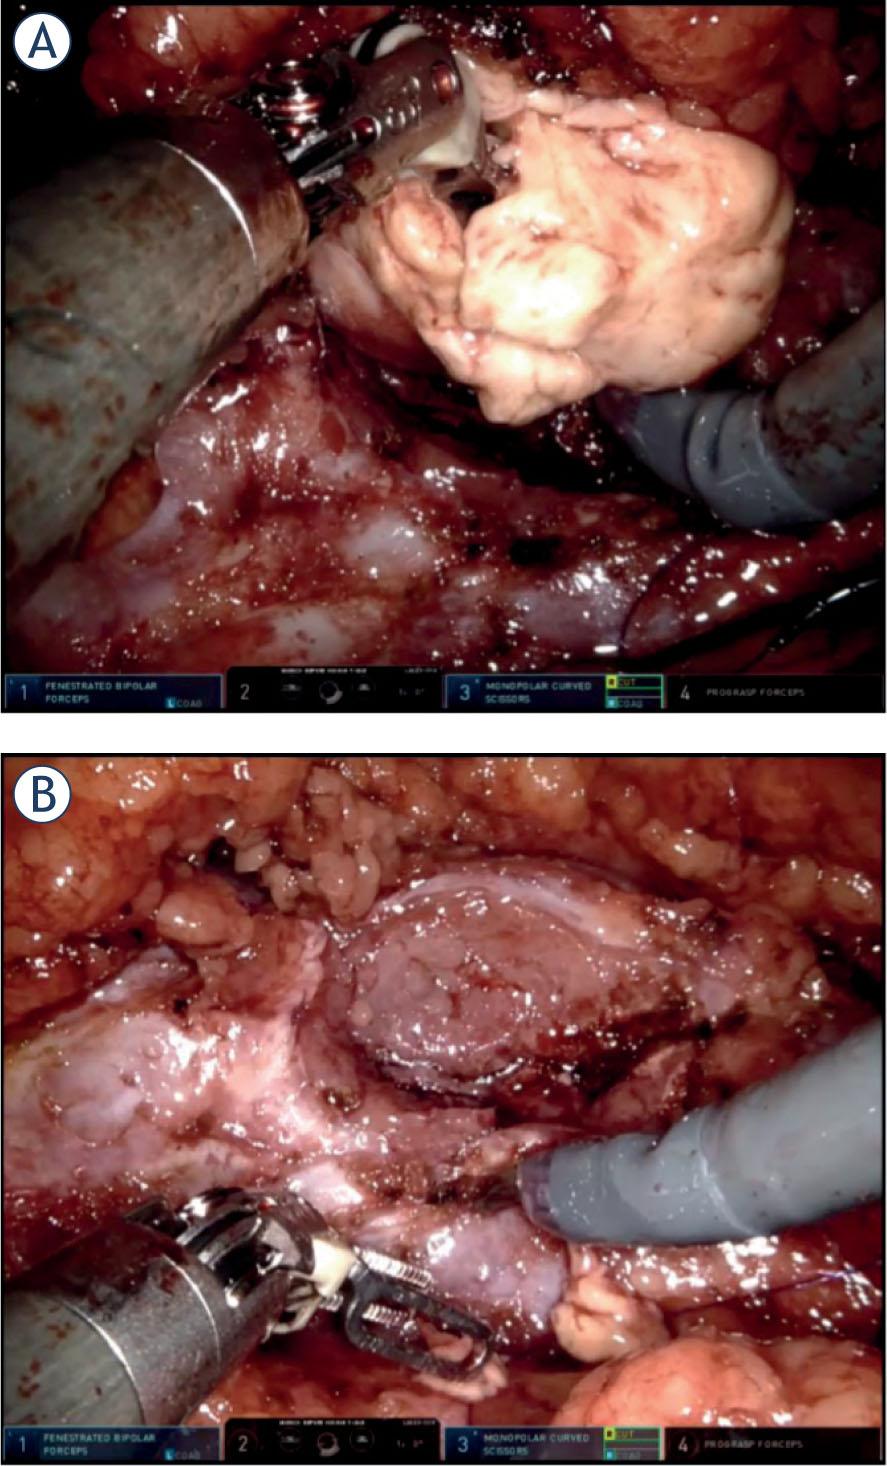

TR was defined as an intraoperative (macroscopic) slit into a tumor during tumor resection and/or tumor manipulation, which could lead to spillage of the tumor cells into the operative field and the abdominal cavity (Figure 1). Our definition is based on the definition by Khene et al. who defined accidental surgical incision into the tumor (ASIT) as “any accidental incision in the tumour or any accidental rupture of tumour surface during handling of the kidney and/or tumor”.5 We want to emphasize a clear distinction between TR (an intraoperative, macroscopic event) and positive surgical margins (a histologic, postoperative, microscopic event).

(A) Example of tumor rupture during enucleation of a renal tumor. (B) Tumor bed after the tumor was completely removed from healthy kidney parenchyma (intraoperative snapshots).